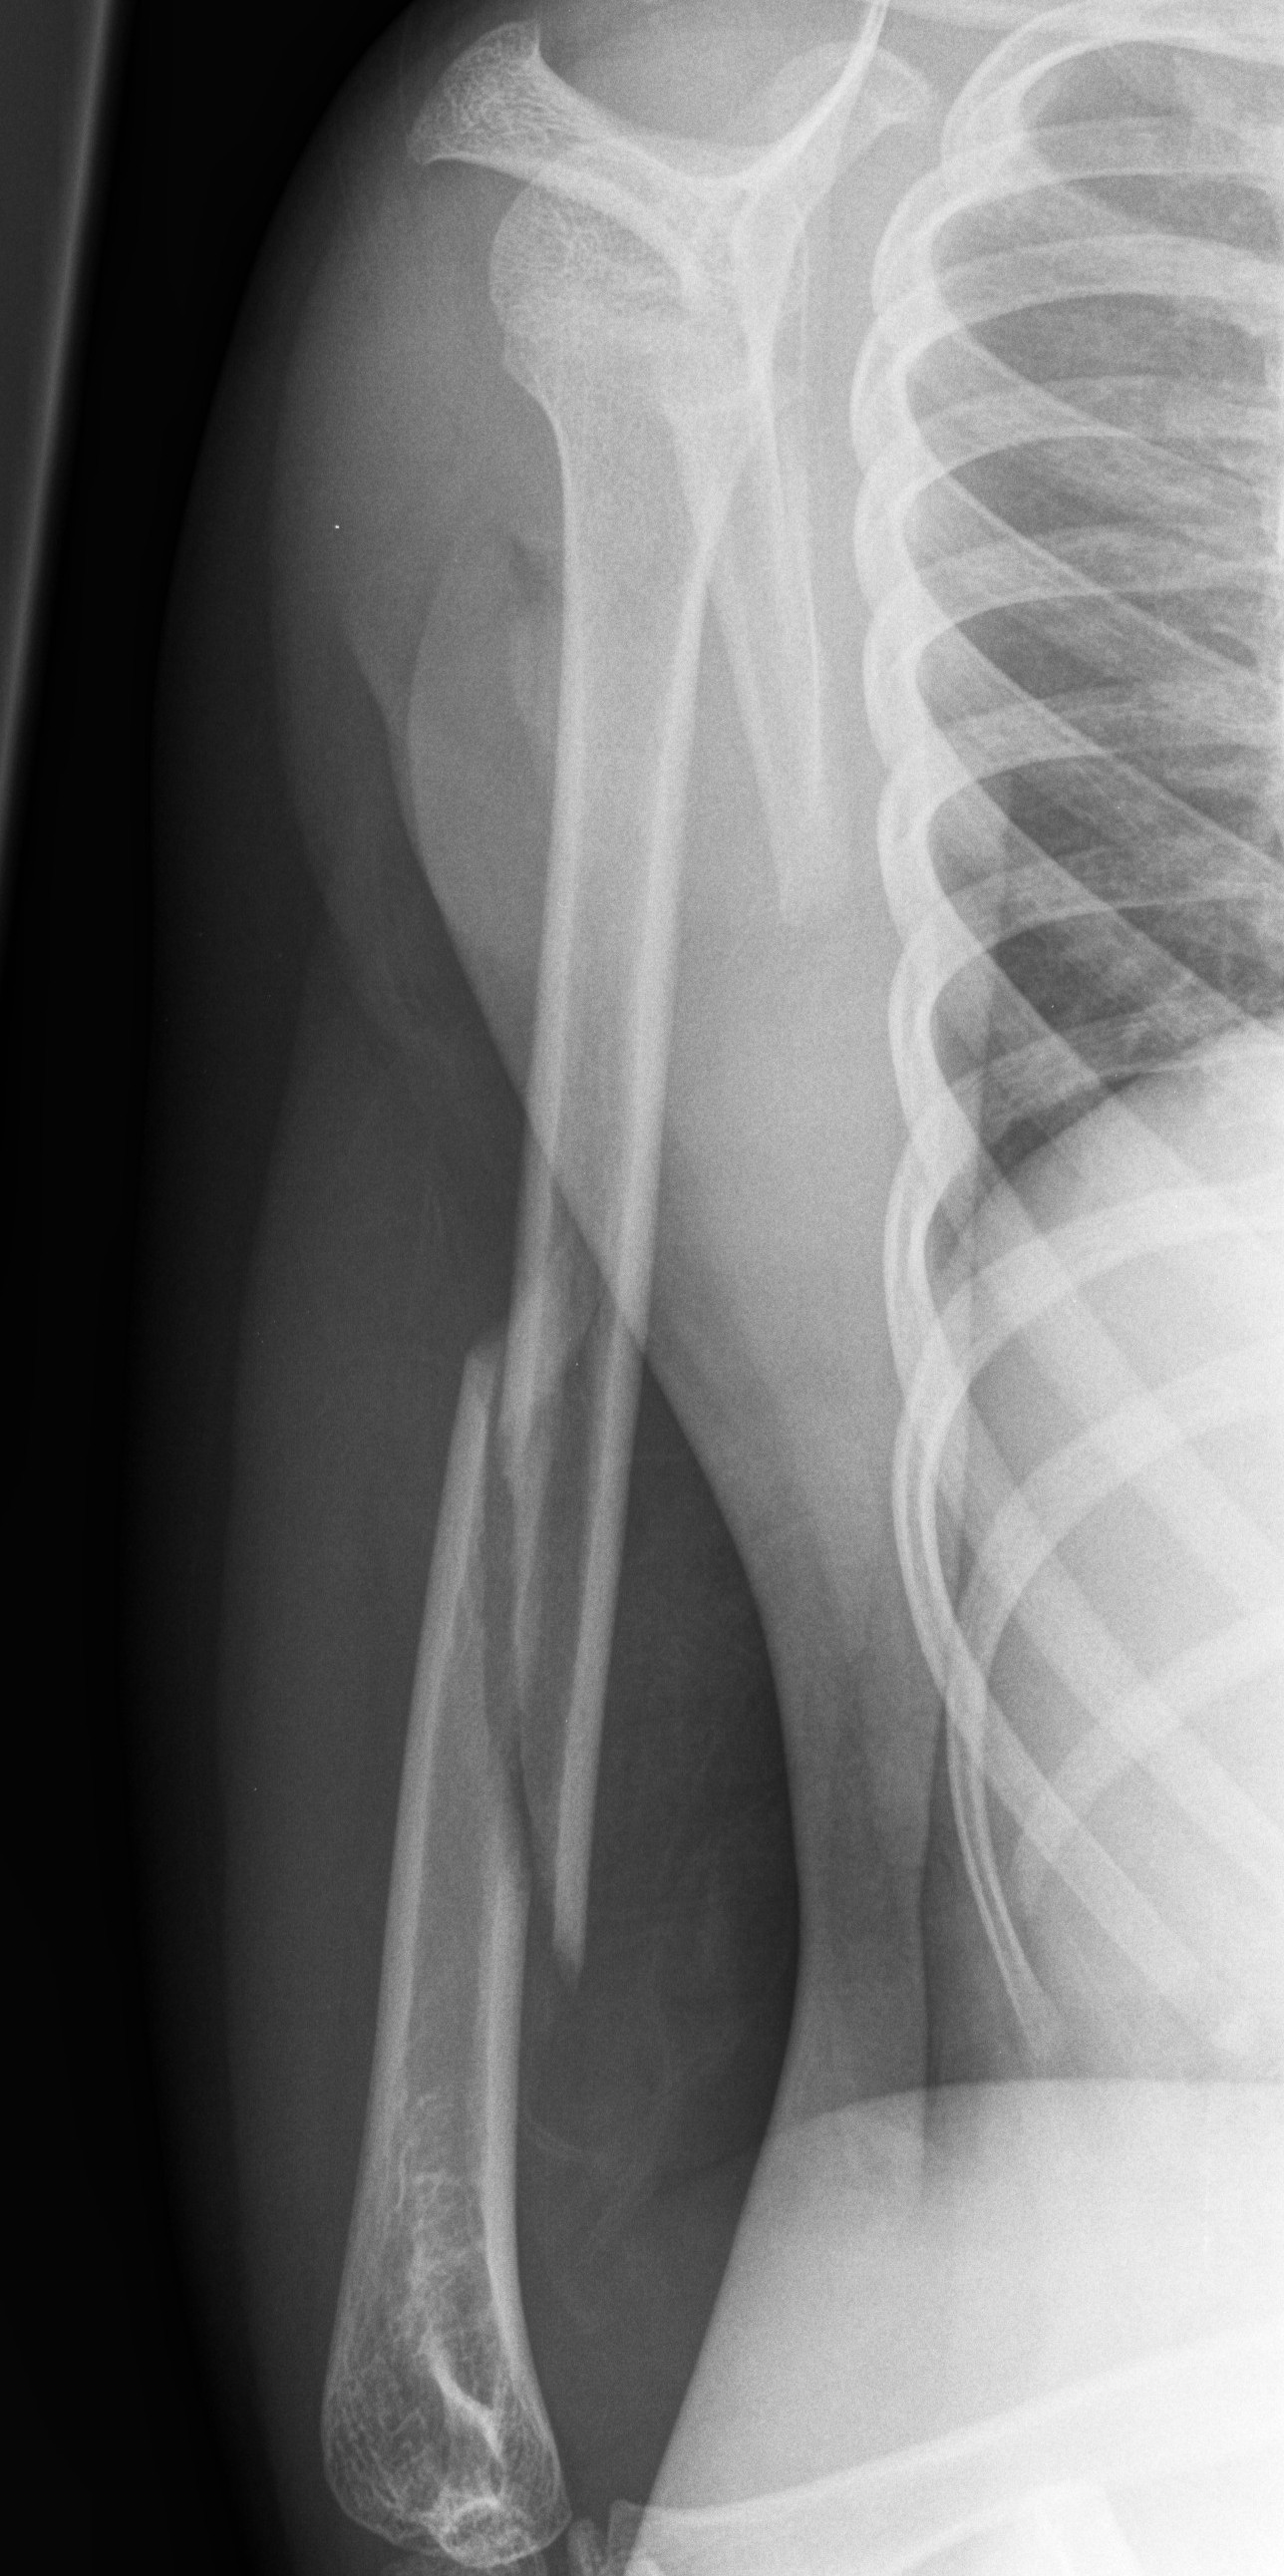

Proximal humerus fractures with > 50% displacement

- Discuss with Orthopaedic team for further management.

Above: Completely displaced proximal humerus fracture